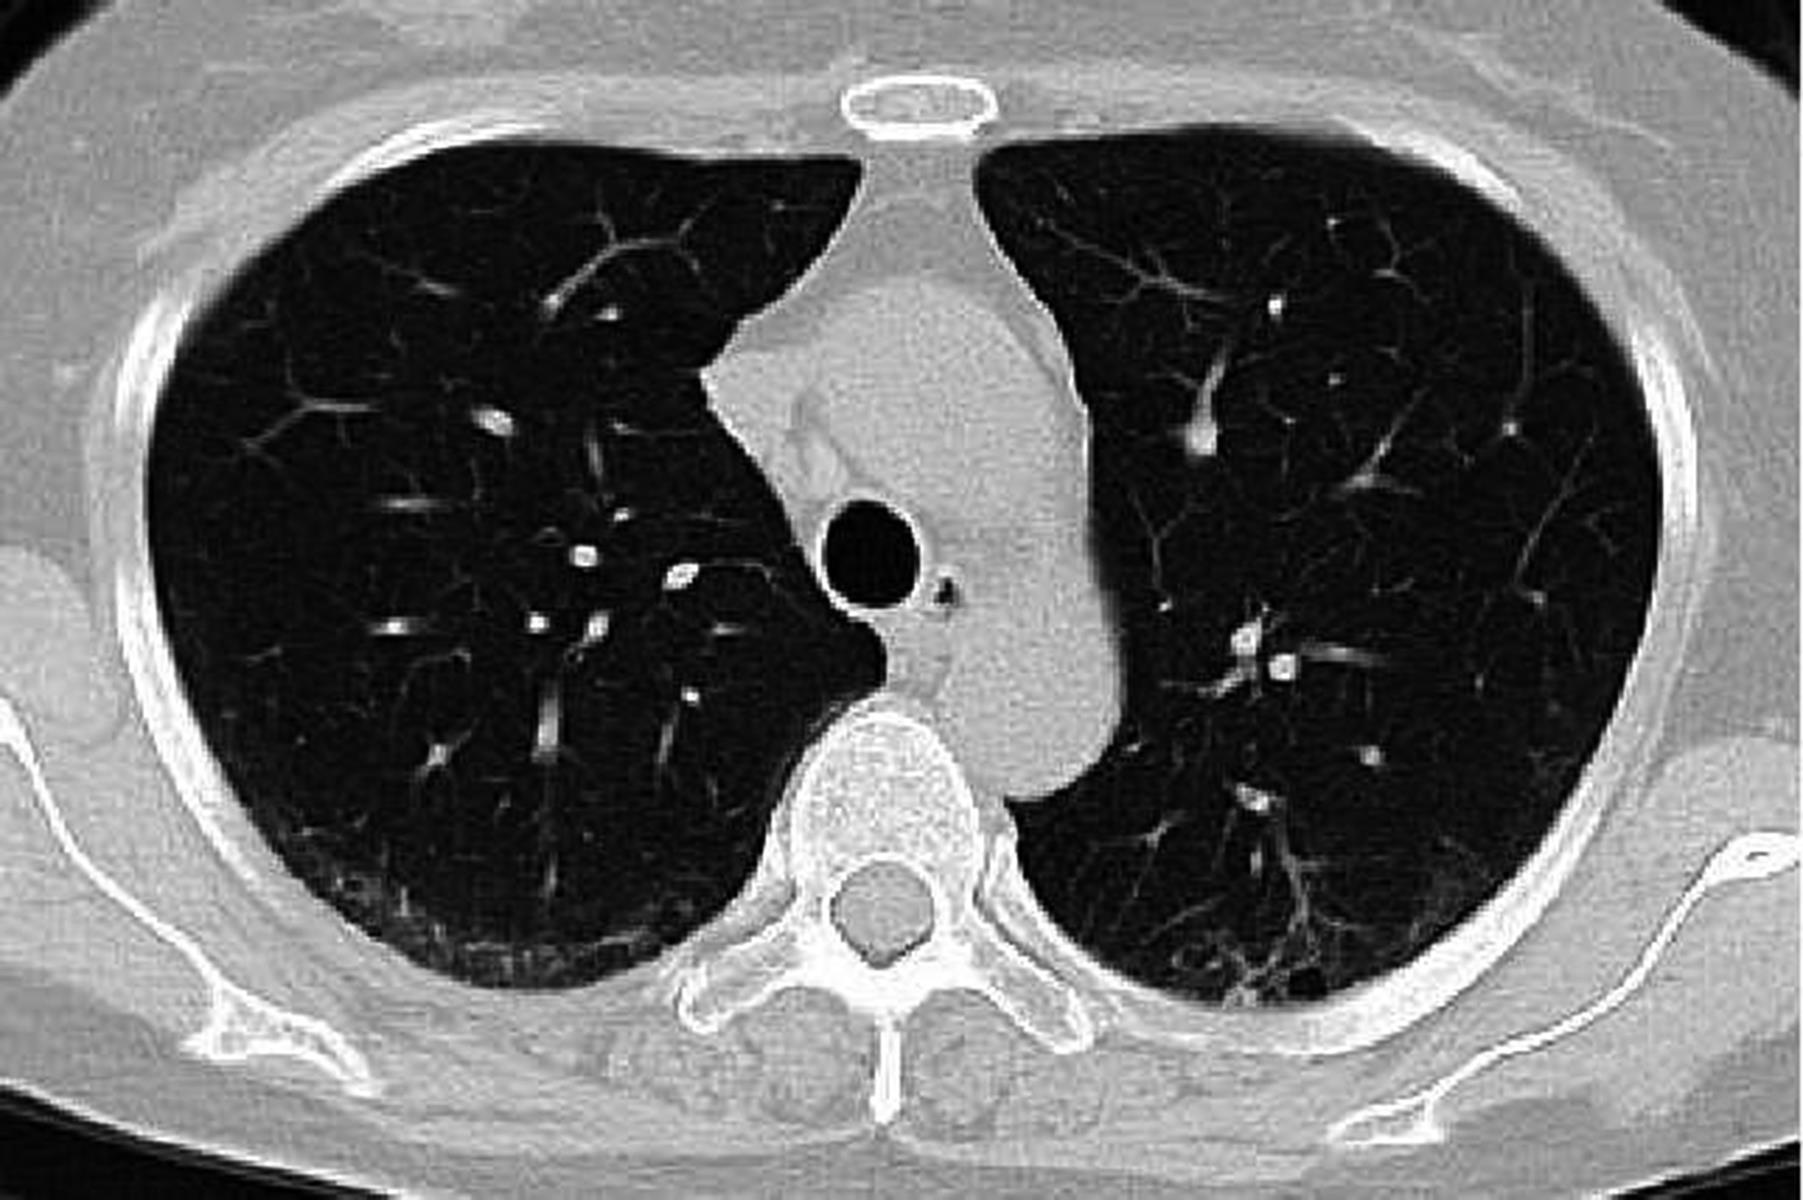

• 系统性红斑狼疮患者肺部影像学特征与疾病活动度相关性研究

2023, 48(11):1351-1355. DOI: 10.13406/j.cnki.cyxb.003353

摘要 (94) HTML (39) PDF 1.35 M (174) 评论 (0) 收藏

摘要:目的 探讨系统性红斑狼疮合并间质性肺病的CT特征与疾病活动度的相关性。方法 纳入131例系统性红斑狼疮相关间质性肺病患者。分析其疾病活动度评分、影像学特征及高分辨CT(high resolution computed tomography,HRCT)肺间质纤维化Kazerooni评分。采用Spearman秩和相关系数检验分析各评分之间的相关性。结果 Kazerooni评分法中的磨玻璃评分与系统性红斑狼疮疾病活动度-2000评分(systemic lupus erythematosus disease activity index-2000,SLEDAI-2000)呈正相关,差异有统计学意义(rs=0.388,P<0.001)。而纤维化评分与SLEDAI-2000评分之间差异无统计学意义(P=0.837)。弥漫性肺泡损伤(diffuse alveolar damage,DAD)组磨玻璃评分得分最高,寻常型间质性肺炎(usual interstitial pneumonia,UIP)组纤维化评分得分最高,差异有统计学意义(均P<0.001)。比较不同间质性肺病(interstitial lung disease,ILD)类型之间SLEDAI-2000评分差异无统计学意义(P>0.05)。结论 胸部HRCT可有助于更全面地评估系统性红斑狼疮疾病情况,对制定治疗方案具有重要意义。